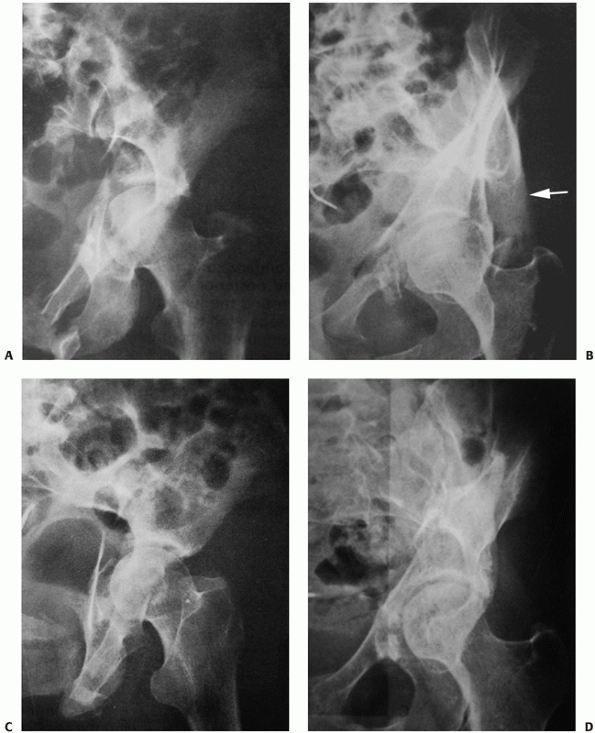

FIGURE 45-3 A 36-year-old female unrestrained driver involved in a motor vehicle accident sustained a fracture of the acetabulum (A) with wide displacement and a particularly sharp spike of posterior column at the greater sciatic notch (arrow)

became hemodynamically unstable shortly after presentation to the emergency department. Subsequent evaluation including angiography (B) revealed a superior gluteal artery injury to be the source of the bleeding, which was successfully treated by embolization (arrow). (Copyright Berton R. Moed, MD.) |

a closed fracture of the acetabulum, occurring alone or in combination

always be sought. However, laceration of the superior gluteal artery

with severe bleeding can be caused by fractures of the acetabulum

having wide posterior column displacement. One must be alert to this

possibility, which is treatable by therapeutic embolization (Fig. 45-3).